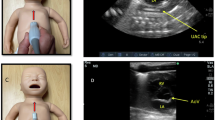

The study was aimed at comparing the accuracy in length of insertion of umbilical arterial catheter in all new born groups stratified according to weight, by using two different methods, that is, Wright et al./Case (Group I): (4 × Body wt (BW) (kg)) +7; Shukla et al./Control (Group II): (3 × BW (kg)) +9.

The babies in both the groups were similar in relation to weight, gender, prematurity and weight subgroups. Under insertion was seen in 8% (4/50) of babies in group I and over insertion was seen in group II where it was 32.6% (16/49). There was a reduction of 82% abnormal insertions and repositioning by using the Wright's formula as compared with the Shukla's formula in preterm babies. Statistically significant reduction in repositioning was seen in all babies <1500 g in Group I and under insertion seen in 8% of babies in group I did not attain statistical significance (P=0.34).

There is no universal formula, which gives the accurate length of placement of an umbilical arterial catheter, but Wright's formula comes closer in neonates with different weight sub groups.